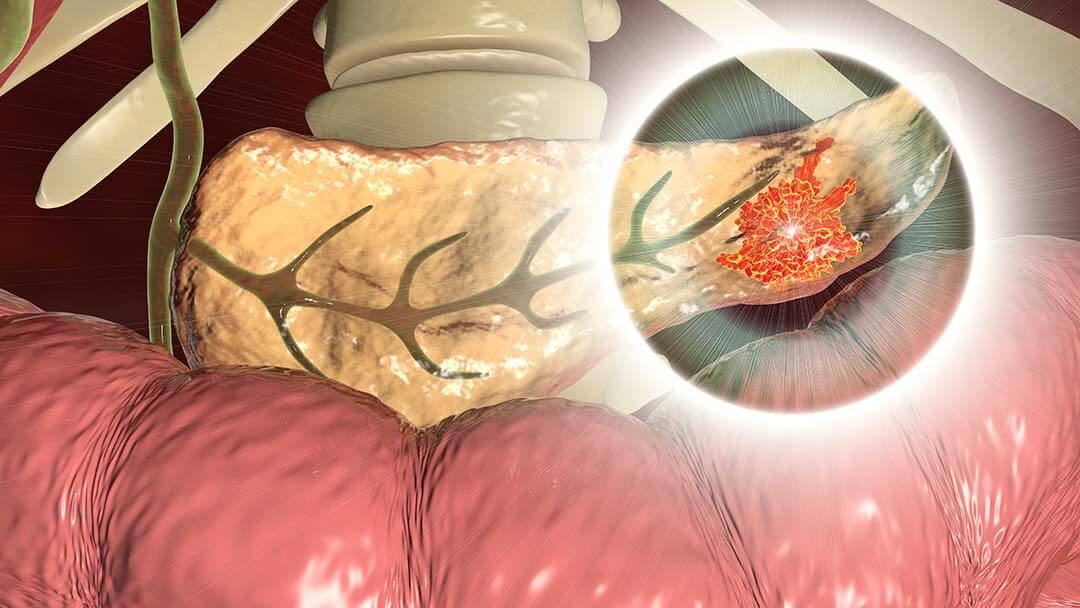

Randomized Phase II Trial of Postoperative Adjuvant Capecitabine and Temozolomide Versus Observation in High-Risk Pancreatic Neuroendocrine Tumors

CONDITION: Metastatic Malignant Neoplasm in the Liver, Pancreatic Neuroendocrine Tumor (pNET)

The purpose of this study is to evaluate recurrence-free survival in participants with resected pancreatic neuroendocrine tumors (pNETs) randomized to treatment with capecitabine + temozolomide (CAPTEM) compared to observation only.

Participants 18 years old and older diagnosed with diagnosed with pancreatic neuroendocrine carcinoma or have metastatic malignant neoplasm in the liver may be eligible for this study.